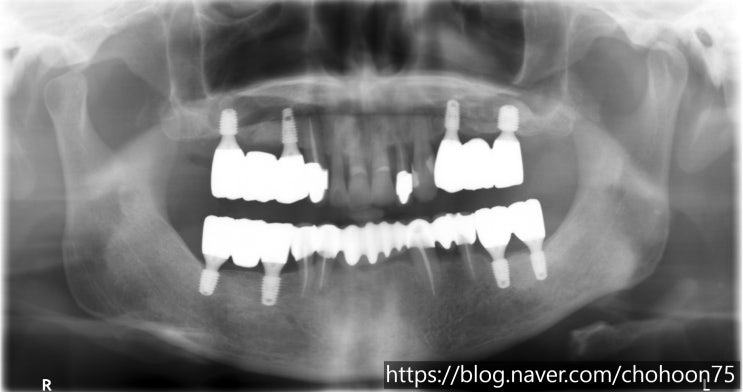

[조훈치과] 틀니 사용 후 임플란트 치료 전환

안녕하세요. 조훈 치과입니다. 오늘은 틀니 사용 후 임플란트로 전환을 하신 60대 환자분의 치료 증례에 대...

[조훈치과] 틀니 사용 후 뼈이식 임플란트 치료 전환

안녕하세요. 조훈 치과입니다. 앞서 2022년 4월, 조훈 치과 블로그에 포스팅하였던 치료 증례로 틀니 사용 ...